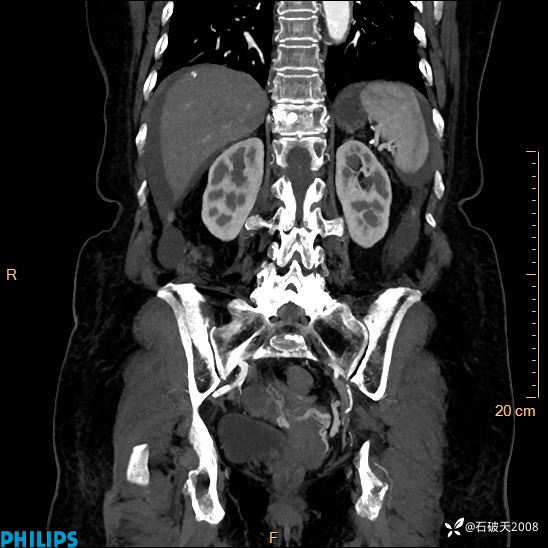

MIP